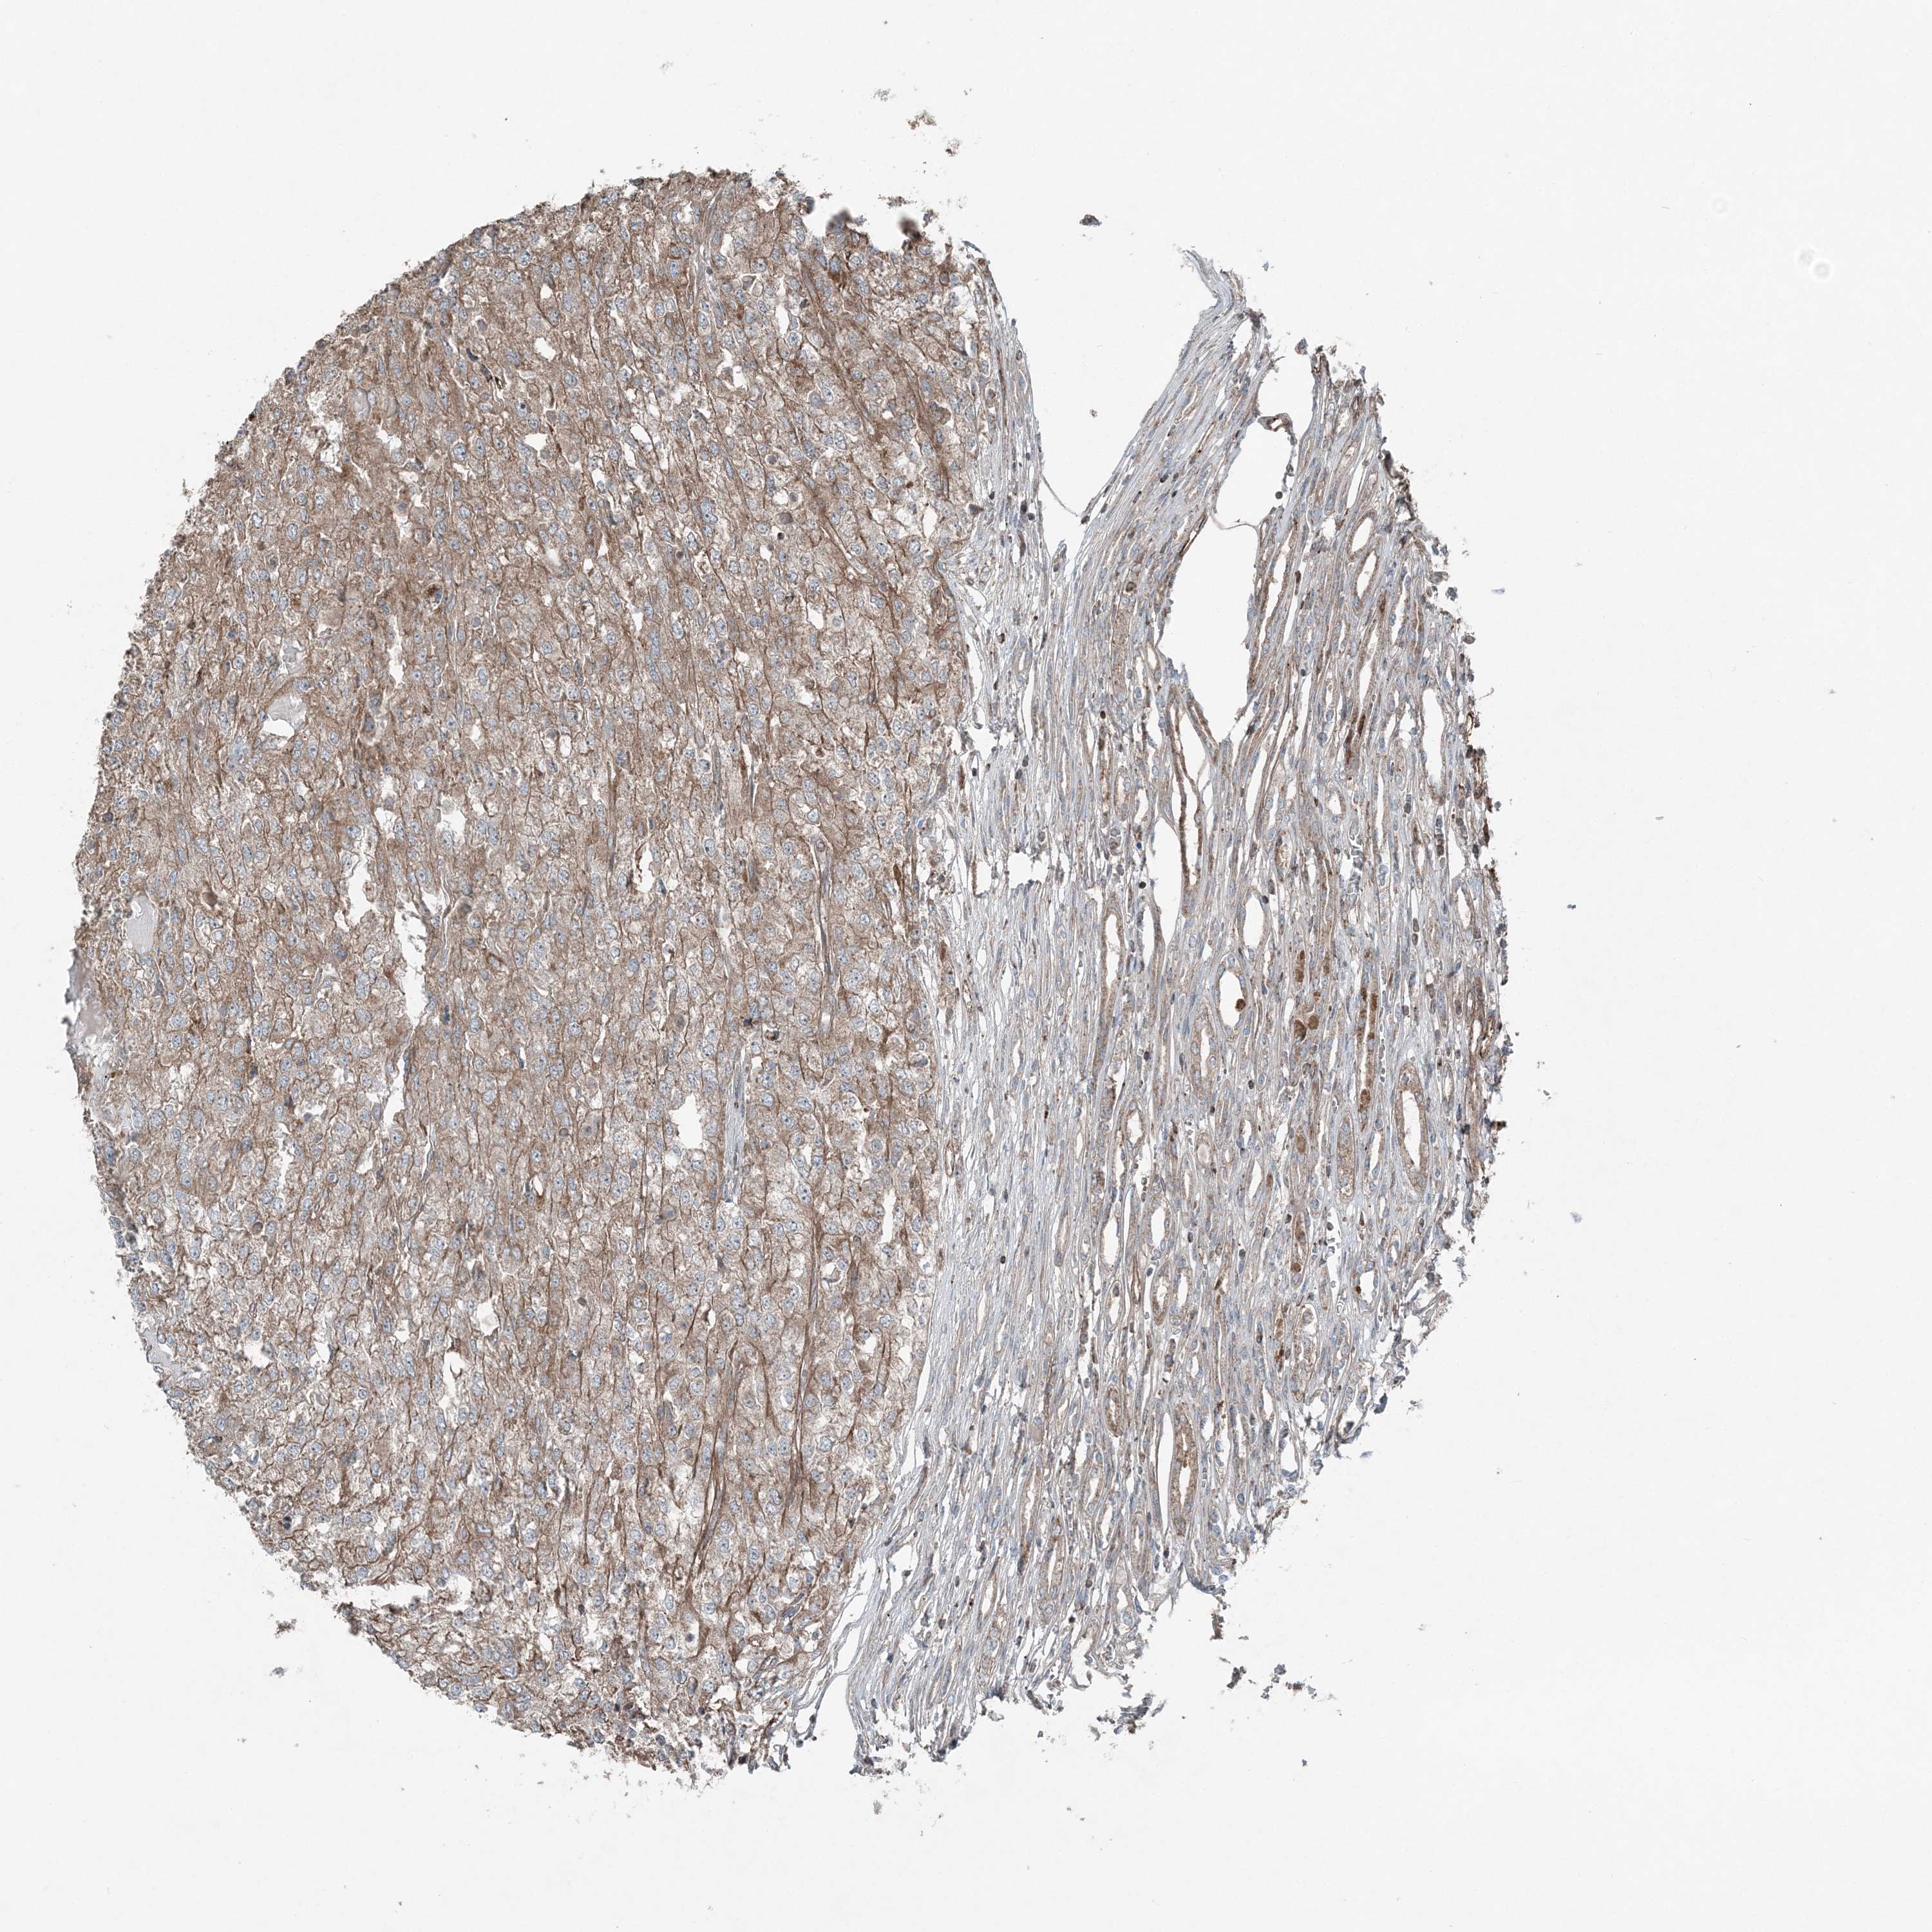

KIDNEY RENAL CLEAR CELL CARCINOMA (TCGA) - Interactive survival scatter ploti

The Survival Scatter plot shows the clinical status (i.e. dead or alive) for all individuals in the patient cohort, based on the same data that underlies the corresponding Kaplan-Meier plots. Patients that are alive at last time for follow-up are shown in blue and patients who have died during the study are shown in red.

The x-axis shows the expression levels (FPKM) of the investigated gene in the tumor tissue at the time of diagnosis. The y-axis shows the follow-up time after diagnosis (years). Both axes are complimented with kernel density curves demonstrating the data density over the axes. The top density plot shows the expression levels (FPKM) distribution among dead (red) and alive patients (blue). The right density plot shows the data density of the survived years of dead patients with high and low expression levels respectively, stratified using the cutoff indicated by the vertical dashed line through the Survival Scatter plot. This cutoff is automatically defined based on the FPKM cutoff that minimizes the p-score. The cutoff can be changed by dragging the vertical line or by entering a cutoff value in the square labeled "Current cut-off".

Under the Survival Scatter plot the p-score landscape (black curve; left axis) is shown together with dead median separation (red curve; right axis). Dead median separation is the difference in median mRNA expression between patients who have died with high and low expression, respectively. It is calculated as follows: median FPKM expression of dead patients with high expression - median FPKM expression of dead patients with low expression. This is intended to aid the user in visually exploring custom cutoffs and the associated p-scores and dead median separation.

Individual patient data is displayed and can be filtered by clicking on one or more of the category buttons on the top of the page. Categories describing expression level and patient information include: high, low, alive, dead, female, male and tumor stages. The scale of the x-axis can be toggled between linear and log-scale by clicking on the "x log" button. Mouse-over function shows TCGA ID, patient information and mRNA expression (FPKM) for each patient.

& Survival analysisi

Kaplan-Meier plots summarize results from analysis of correlation between mRNA expression level and patient survival. Patients were divided based on level of expression into one of the two groups "low" (under cut off) or "high" (over cut off). X-axis shows time for survival (years) and y-axis shows the probability of survival, where 1.0 corresponds to 100 percent.

KY is not prognostic in Kidney Renal Clear Cell Carcinoma (TCGA)

TCGA RNA samplesi

RNA-seq data is reported as average FPKM (number Fragments Per Kilobase of exon per Million reads), generated by the The Cancer Genome Atlas (TCGA) .

Normal distribution across the dataset is visualized with box plots, shown as median and 25th and 75th percentiles. Points are displayed as outliers if they are above or below 1.5 times the interquartile range. FPKM values of the individual samples are presented next to the box plot.

Average pTPM 0.2

Number of samples 521